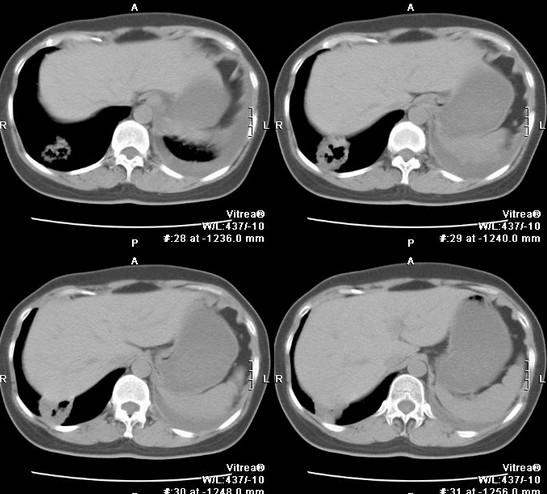

胸部CT扫描多呈类圆形的厚壁脓腔,脓腔内可有液平面出现,脓腔内壁常表现为不规则状,周围有模糊炎性影。

吸入性肺脓肿在早期化脓性炎症阶段,其典型的X线征象为大片浓密模糊炎性浸润阴影,边缘不清,分布在一个或数个肺段,与细菌性肺炎相似。脓肿形成后,大片浓密炎性阴影中出现圆形透亮区及液平面。在消散期,脓腔周围炎症逐渐吸收,脓腔缩小而至消失,最后残留少许纤维条索阴影。慢性肺脓肿脓腔壁增厚,内壁不规则,周围炎症略消散,但不完全,伴纤维组织显著增生,并有程度不等的肺叶收缩,胸膜增厚。纵隔向患侧移位,其他健肺发生代偿性肺气肿。

血源性肺脓肿在一肺或两肺边缘部有多发的散在小片状炎症阴影或边缘较整齐的球形病灶,其中可见脓腔及液平面。炎症吸收后可呈现局灶性纤维化或小气囊。